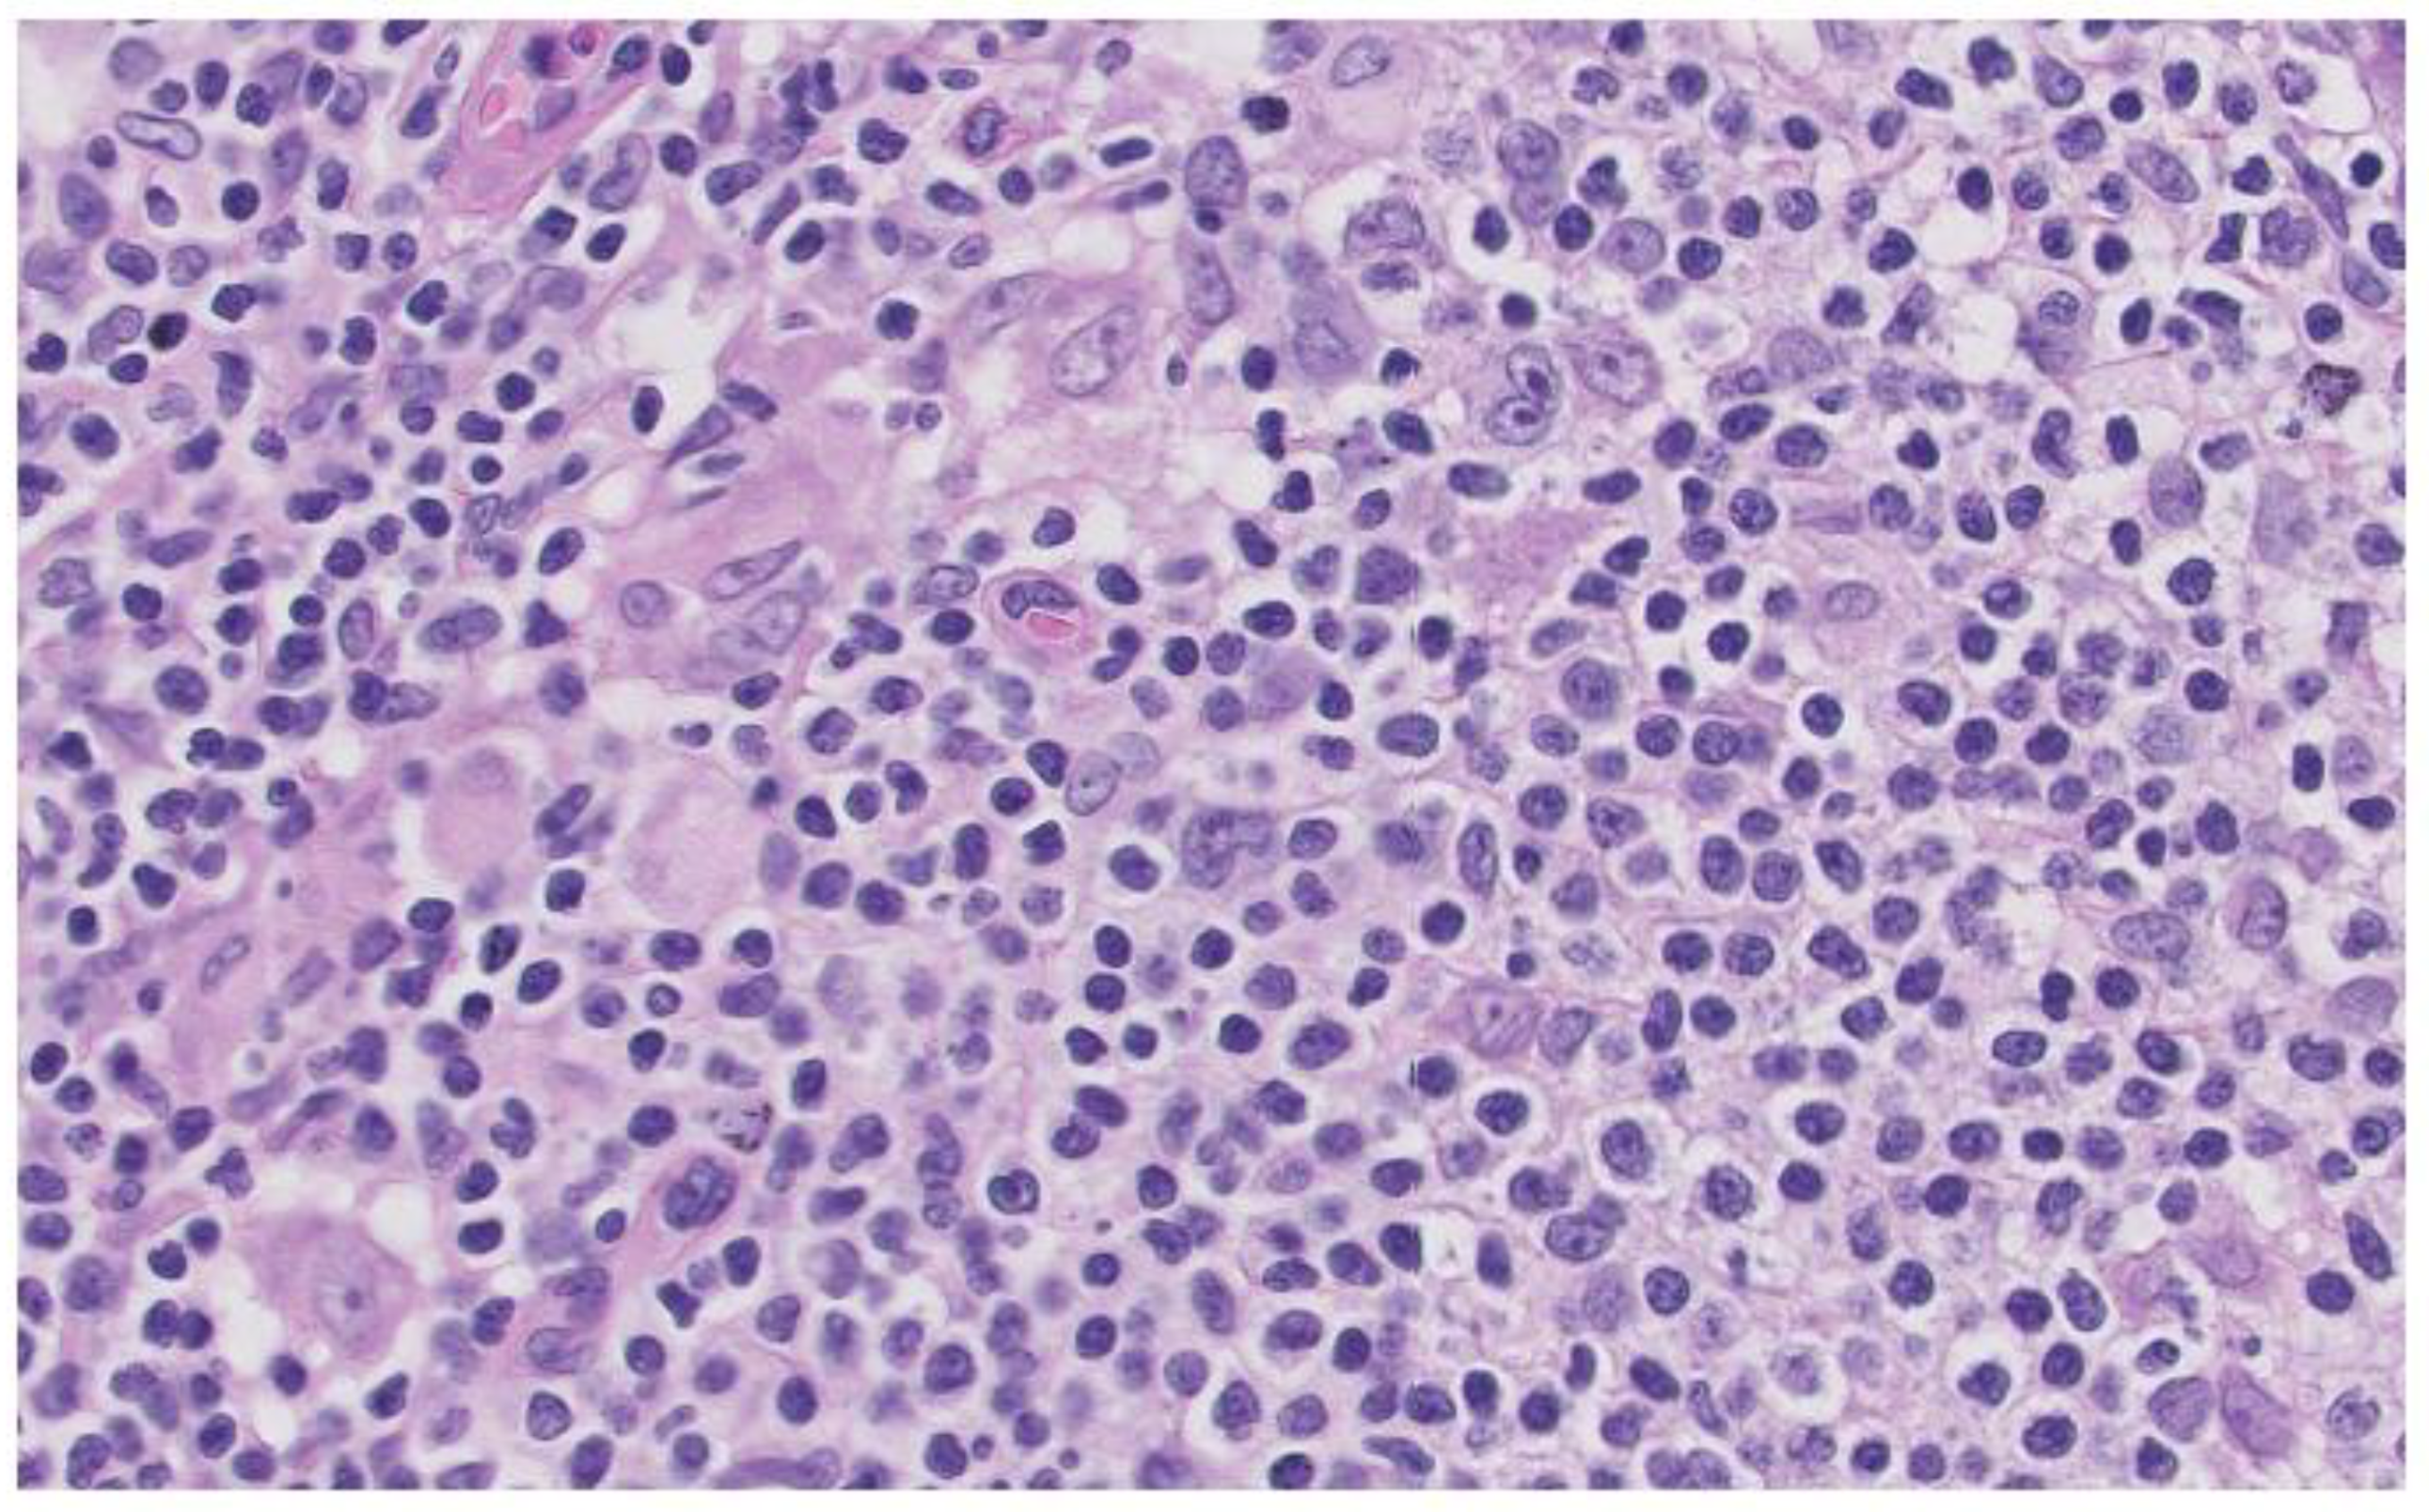

BM biopsy revealed isolated ample cytoplasmic cells with one or more nuclei with prominent nucleoli expressing CD15, CD30, PAX5 and EBER as well as images of hemophagocytosis with hardly any residual normal hematopoietic tissue. Reed-Sternberg were observed. In addition, large numbers of polytypic plasma cells and a striking increase in CD3/CD8 positive small T lymphocytes and abundant loose epithelioid histiocytes are also shown, with no granuloma formation. The observed cells do not express CD20 or CD79a, and no positive Human Herpes Virus 8 (HHV8) cells or increased number of blasts were observed (Image 1).

These findings make the diagnosis more likely as Hodgkin’s lymphoma (HL)

Image 1. Bone marrow biopsy. (A): Hematoxylin eosin stain X 40. (B): EBER in situ hybridization. (C): PAX5. (D): CD30.